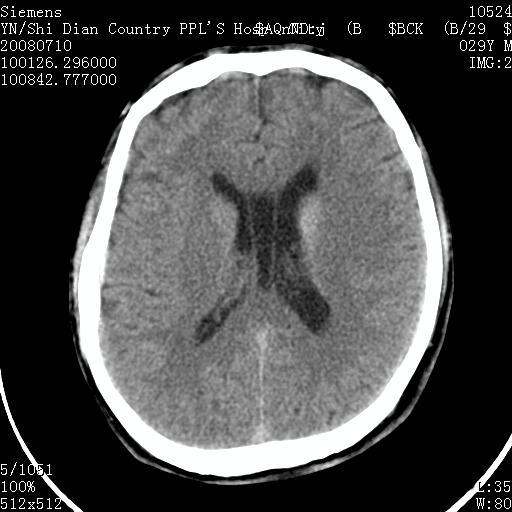

以下是引用随光逐影在2008-7-10 15:19:00的发言:[br]1)考虑左侧尾状核钙化。2)透间隔间腔与vergae腔并存。

以下是引用卜一在2008-7-10 16:43:00的发言:[br]1)考虑左侧尾状核钙化。2)透间隔间腔形成。支持!